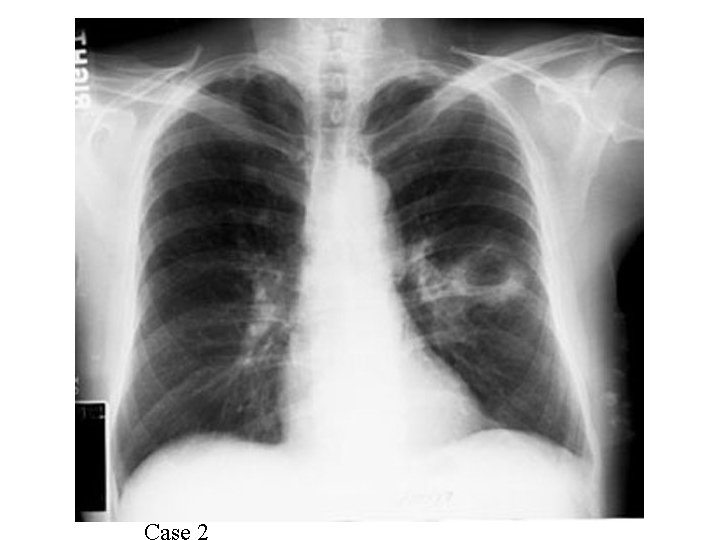

Case 1